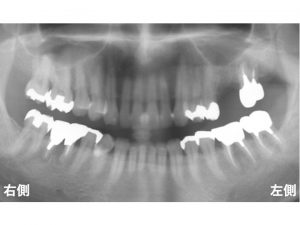

以下は治療前です。

上顎の右側に2歯の欠損、

上顎左側の奥歯が4歯欠損しています。

問題となるのは、この欠損部だけではありません。

上顎の前歯です。

上顎前歯部もグラグラで抜けそうです。

上顎右側は、本当に骨吸収が大きく、

インプラント治療が難しい状態でした。

以下の緑線が上顎洞です。

次に

現在の骨を赤線で記載します。

骨の高さが非常に少ないです。

このままであると

本当に短いインプラントしかできません。

以下のようでは、インプラントはきちんとできません。

そこで上顎洞内部に人工骨を入れます。

インプラントを埋入します。

以下が実際のインプラント手術後です。